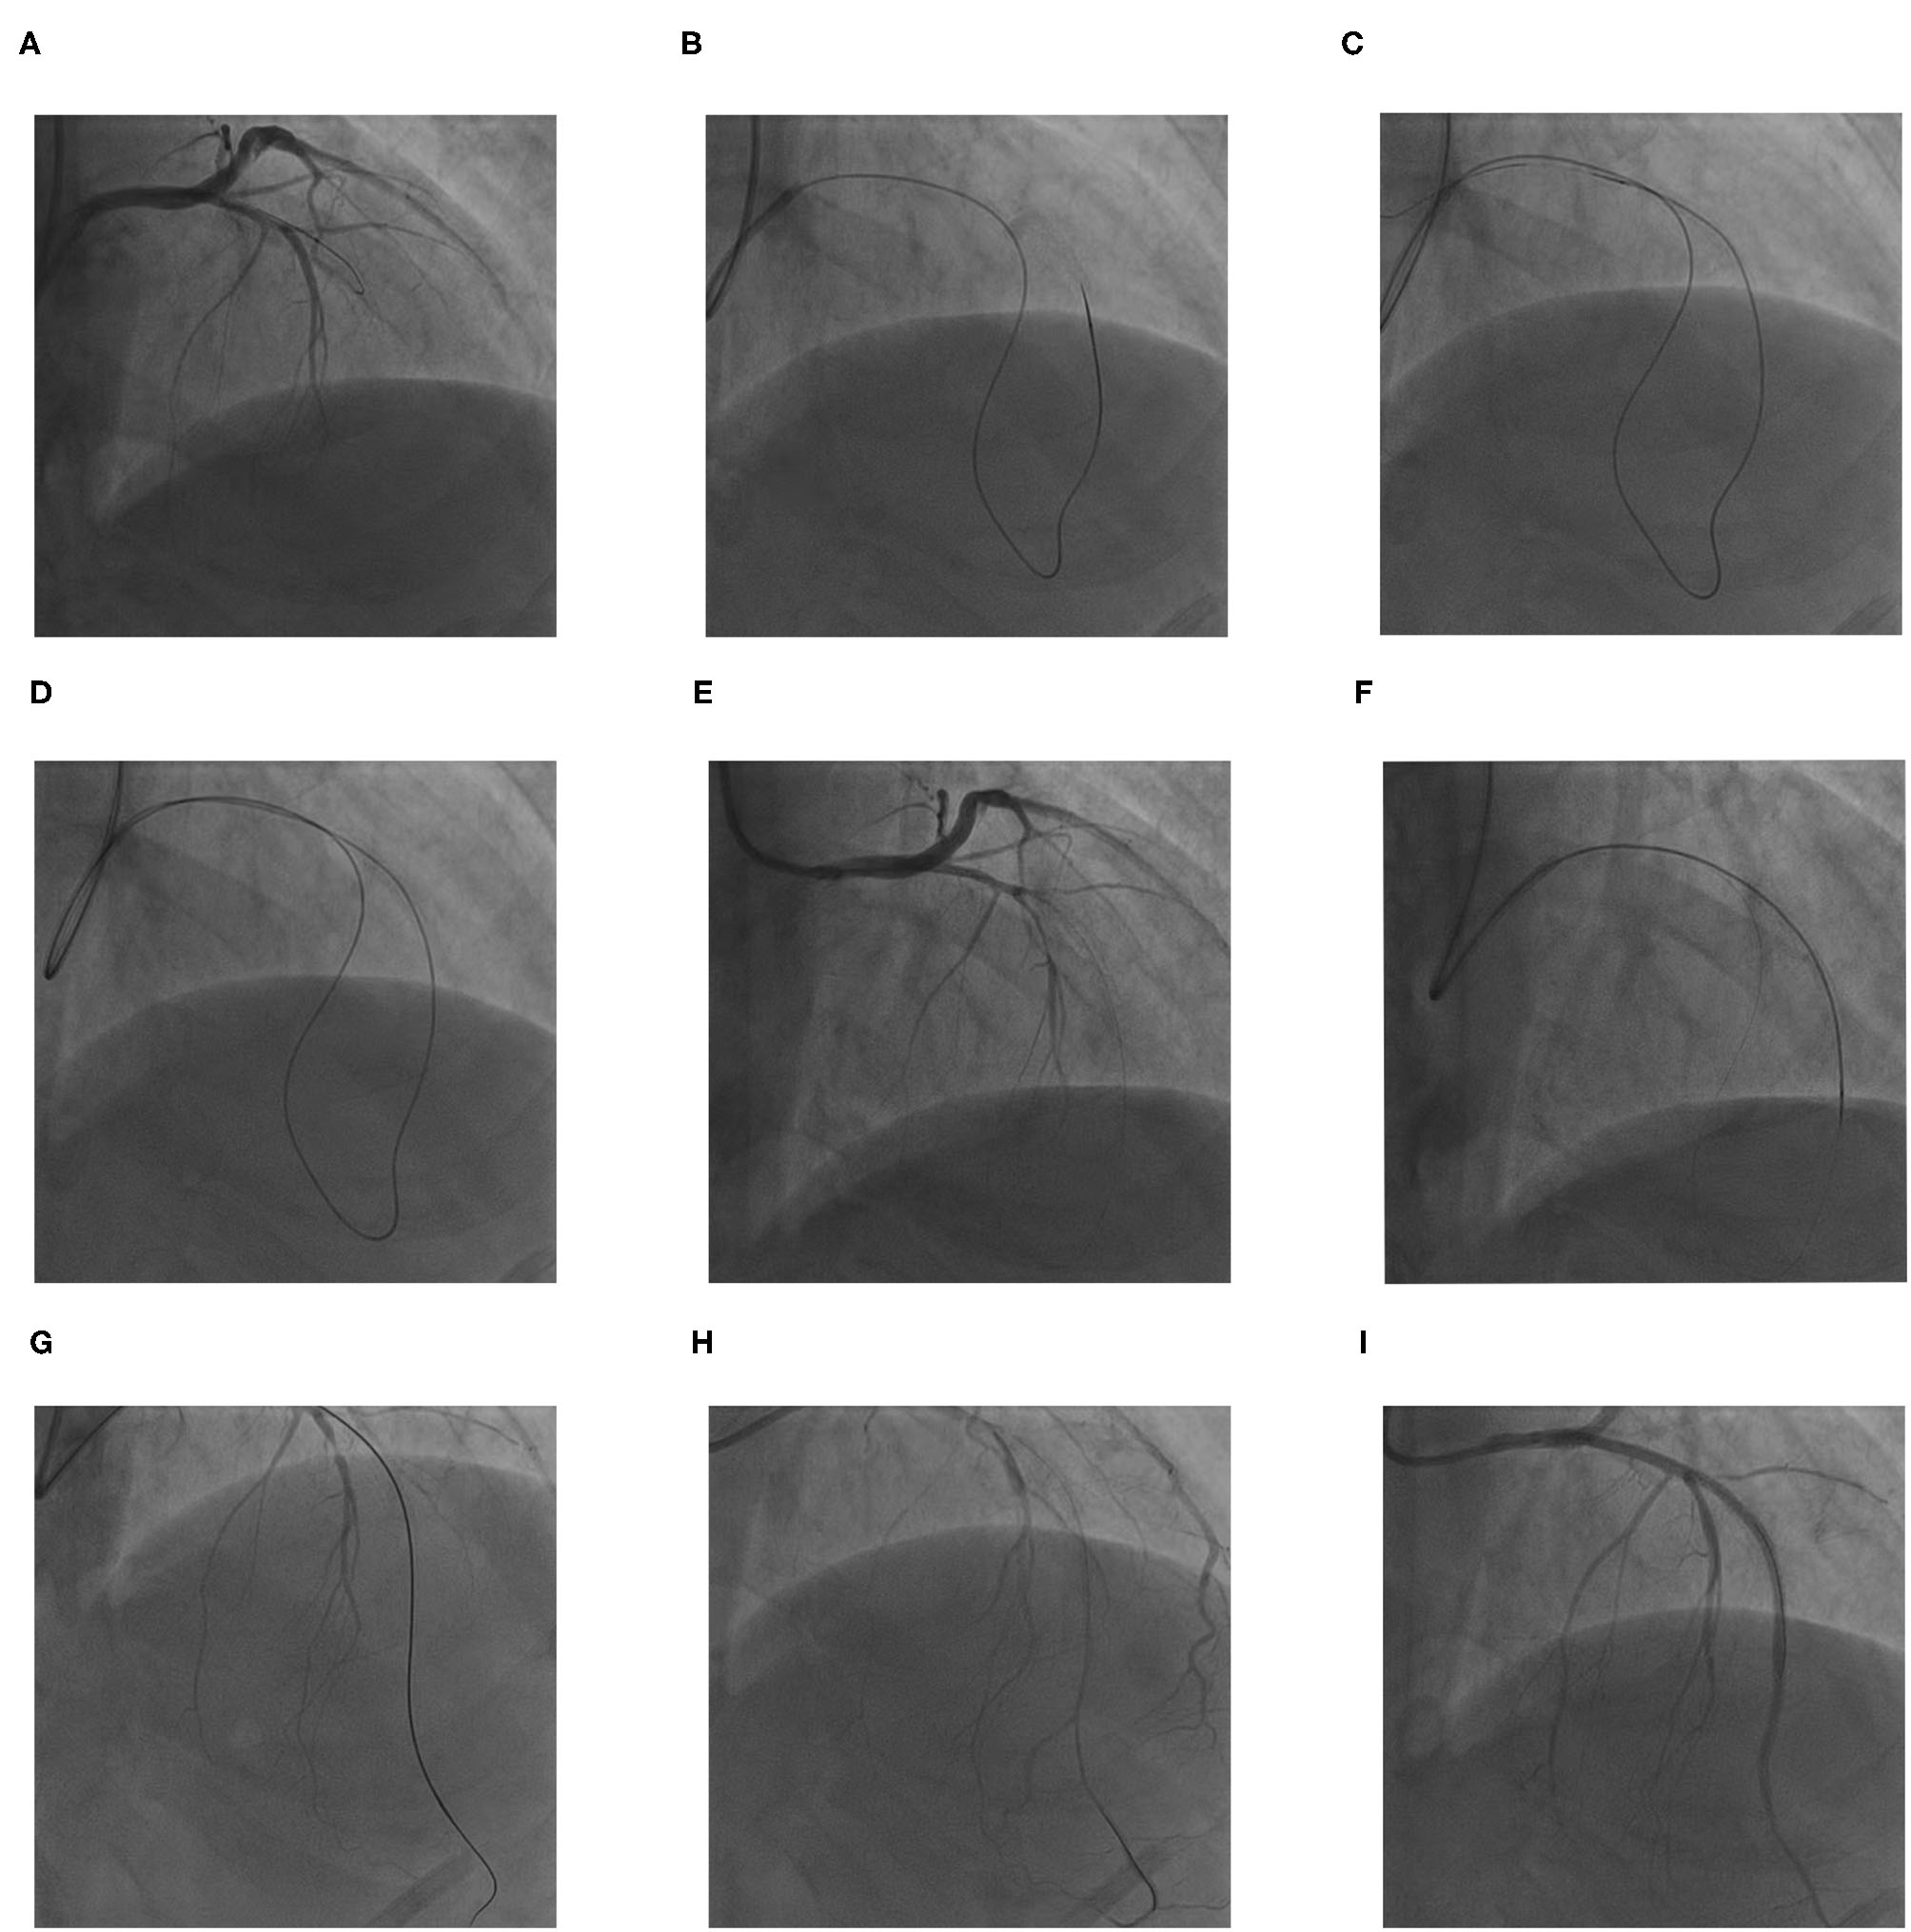

Coronary artery bypass graft (CABG) surgery was advised for the patient according to the coronary angiography. The patient was thoroughly informed of the risks of the CTO-PCI; he refused CABG surgery and accepted the risks of PCI. PCI for the LAD CTO was then attempted. After repeated attempts at antegrade access failed (Figure 2A), the retrograde approach was tried. The 6-Fr JL 3.5 guiding catheter of radial artery continued to be used because the patient's radial spasm made changing sheaths difficult. In addition, there were concerns that his poor left-ventricular function would make lying flat over a long period risky; therefore, femoral access was the back-up site if transradial access failed. The retrograde wire (SION black 190, Asahi) was advanced through the septal collateral with the microcatheter (Corsair 150, Asahi), reaching the distal CTO lesion (Figure 2B). Then, the retrograde Sion wire was exchanged for a PILOT150 (Abbott) wire. It crossed the CTO segment successfully and was threaded into the guiding catheter retrogradely. The microcatheter was subsequently advanced over the wire into the guiding catheter (Figures 2C,D). A 300-cm RG3 wire (Asahi) was externalized via the microcatheter (Figure 2E). Then, the microcatheter was withdrawn retrogradely and advanced to the proximal LAD through the septal collateral over the wire antegradely. The RG3 wire was removed (Figure 2F). Then, the microcatheter was introduced to the distal LAD. Afterward, the antegrade wire (SION black) was advanced through the lesion. When the wire was confirmed to be in the true lumen by an angiogram, the microcatheter was removed (Figures 2G,H), and three drug-eluting stents were deployed successively at mid-LAD (Figure 2I). The final angiogram showed Thrombolysis in Myocardial Infarction (TIMI) flow grade 3 in the distal LAD.

Figure 2

The procedures for retrograde percutaneous coronary intervention (PCI) of LAD chronic total occlusion (CTO). (A) The antegrade wire could not cross the CTO lesion. (B) The retrograde soft wire was advanced through the septal collateral with the microcatheter reaching the distal CTO lesion. (C,D) The retrograde soft wire was exchanged for a stiff wire via microcatheter, which crossed the CTO segment into proximal LAD true lumen, and threaded into the antegrade catheter with microcatheter retrogradely. (E) A 300-cm RG3 wire was externalized via the microcatheter. (F) The microcatheter was inserted into the proximal LAD through the septal collateral antegradely; the RG3 wire was removed. (G,H) The microcatheter was introduced to the distal LAD; the antegrade wire was advanced through the lesion. When the wire was confirmed in true lumen by angiogram, the microcatheter was removed. (I) Three drug-eluting stents were deployed at mid LAD successively.